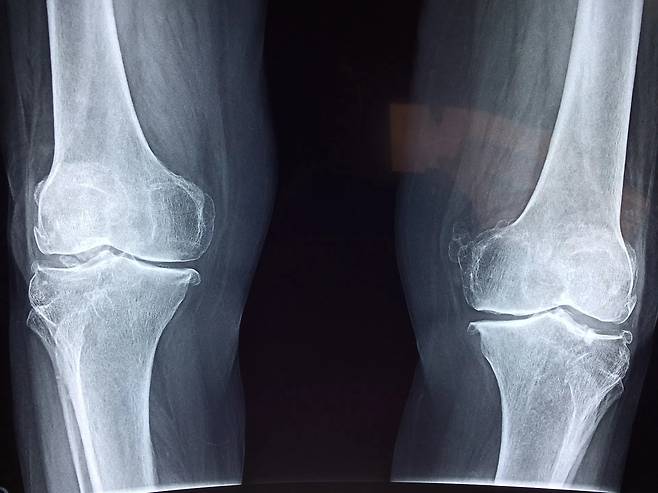

관절염은 단순히 나이가 들어서 생기는 관절의 마모가 아니다. 실제로는 몸속 염증이 오래 쌓이면서 연골과 주변 조직이 손상되고, 통증과 부종이 반복되는 만성 염증 질환이다. 약물치료가 기본이지만, 식단을 잘 관리하면 염증 신호를 크게 줄이고 관절의 회복 속도를 높일 수 있다. 그중 과학적으로 가장 많은 연구가 된 대표 식품이 바로 연어다.

식사 외에도 관절의 염증을 줄이는 생활습관이 중요하다. 하루 15분 이상 가벼운 스트레칭이나 수중 걷기를 하면 관절 내 윤활액 순환이 촉진돼 통증이 줄어든다. 체중이 1kg 늘면 무릎에 가해지는 하중이 4kg 늘기 때문에, 적정 체중 유지가 필수다. 수면 중에는 염증 조절 호르몬인 코르티솔이 분비되므로, 7시간 내외의 숙면이 회복에 도움이 된다.